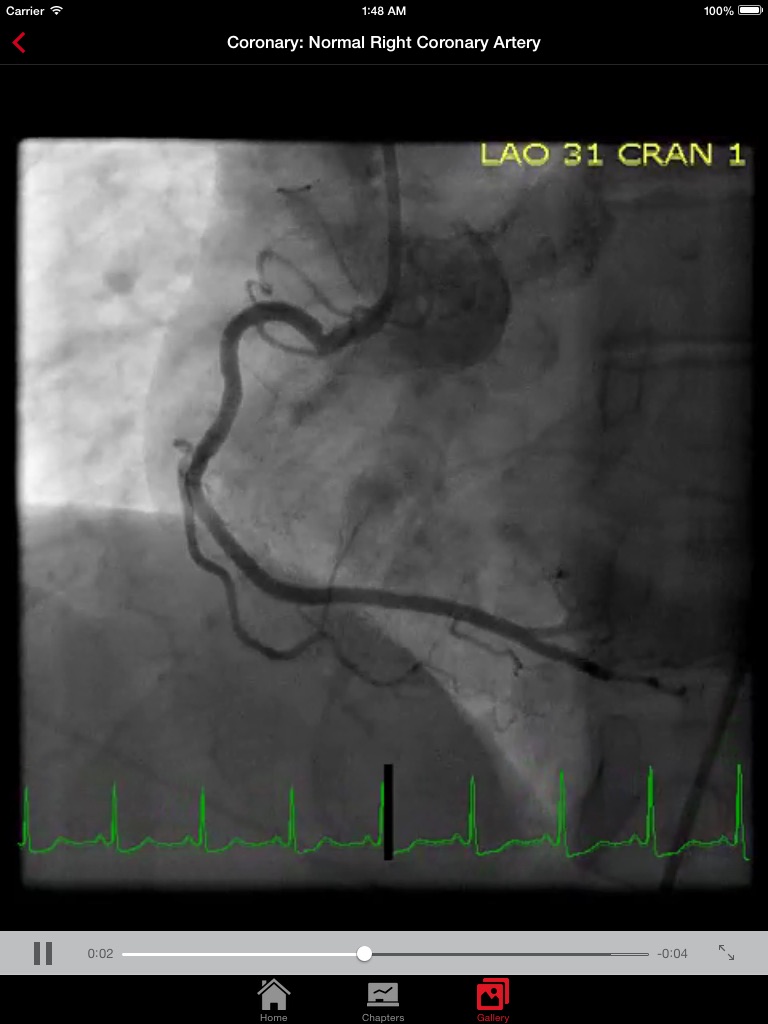

CathSource (from the creators of ECGsource) is an up-to-date medical reference devoted exclusively to cardiac catheterization and angiography. Developed by practicing Interventional Cardiologists for both specialists and trainees in the field of cardiovascular disease, CathSource offers the following content: * Searchable index of specialized topics including: Normal Coronary Anatomy Anomalous Coronary Arteries Coronary Artery Aneurysms Standard Views of Angiography Coarctation of the Aorta Femoral Artery Access for Angiography Radial Artery Access for Angiography Intravascular Ultrasound (IVUS) Optical Coherence Tomography (OCT) Fractional Flow Reserve (FFR) Hemodynamics: Intracardiac Pressures Hemodynamics: Intracardiac Waveforms Hemodynamics: Cardiac Output Hemodynamics: Intracardiac Shunts Hemodynamics: Aortic Stenosis Hemodynamcis: Aortic Regurgitation Hemodynamics: Mitral Stenosis Hemodynamcis: Mitral Regurgitation Hemodynamcis: Constriction Hemodynamics: Restriction * Searchable database containing more than 30 videos (coronary angiograms, ventriculograms, and aortograms) of both common and rare findings in the cardiac catheterization lab * Searchable database of over 65 images including hemodynamic formulas, tables, and figures CathSource provides a detailed overview of important cardiac catheterization and angiography topics, incorporating educational images/videos as well as reviews of pertinent medical literature. CathSource is the ideal application to assist you in understanding and recognizing cardiovascular pathology in the catheterization lab.